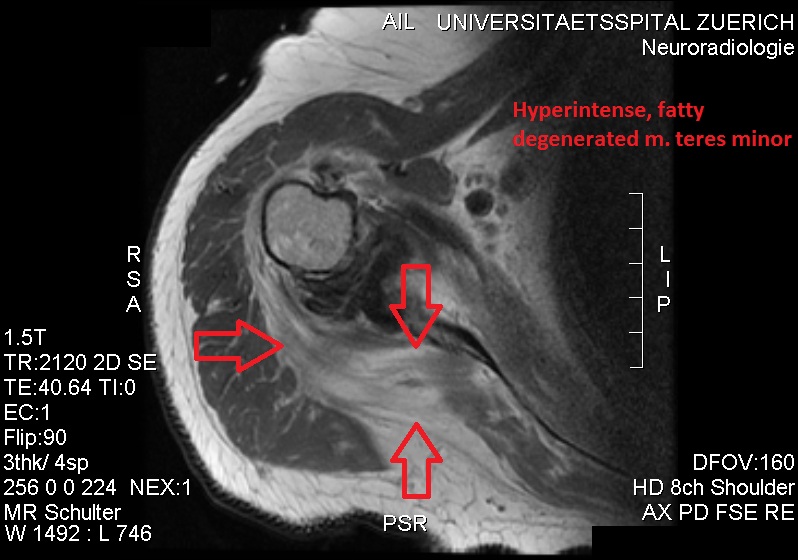

고신호 강도를 보이는 지방 변성 소원근.

초음파검사(ultrasonography)는 소원근의 지방 퇴행성 위축을 탐지하는 도구이며, 다친 근육의 에코 발생(echogenicity)가 늘어나고 근육 부피의 약간의 감소가 보이기도 한다. 자기 공명 영상(MRI)는 신경성 근위축(neurogenic muscle atrophy) 진단에 유용하다. 외상 후 세포외수종(extracellular edema)은 신경 손상을 일으키며, MRI T2 강조 영상(T2-weighted MRI) 결과에서의 신호 강도(signal intensity) 증가와 T1 강조 영상 결과물에서의 신호 강도 정상을 보인다. 후방상완골선회동맥 압축과 스트레스를 유발하는 팔 위치나 조작으로 인한 혈류 감소는 도플러 초음파 검사(Doppler ultrasonography)로 진단할 수 있다. 혈관 옆 신경이 탐지된다. 팔을 들어올린 자세에서는, 액와신경혈관다발(axillary neurovascular bundle)이 삼각근을 관통하기 바로 직전에 후방 겨드랑 주름(posterior axillary fold)에서 보일 수 있지만, 팔을 내린 자세에서는 후방 코스(posterior course)가 잘 보인다. 동맥의 자세한 진단을 위하여, MR 혈관 조영술(MR angiography)이 필요하다. 초음파 검사는 무게를 갖는 공간을 탐지하는 것이다. 추가적인 근전도 검사(electromyography)는 신경 전도(nerve conduction) 속도 감소와 관련 근육의 신경 제거(denervation) 상태를 밝혀내는 데 유용하다.[12][6]